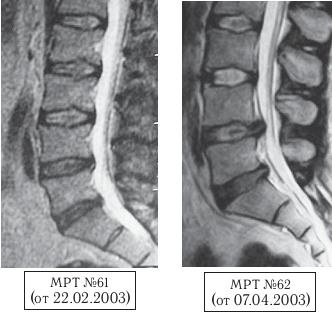

Ознакомившись с примерами МРТ-снимков пациентов, прошедших курсы лечения вытяжением, можно проследить, какие последствия бывают после применения метода вытяжения. Вот, к примеру, типичный случай развития дегенеративно-дистрофического процесса после применения данного метода.

История болезни данного пациента довольно типична. В январе 2003 года после падения (подскользнулся, упал на спину) появились боли в пояснице. В феврале ему сделали МРТ (МРТ № 61). В марте того же года данный мужчина поехал по путёвке на курорт лечить спину, где прошёл курс вытяжения позвоночника, после чего к болям в пояснице присоединились и боли в правой ноге. В апреле того же года ему вновь сделали контрольный снимок МРТ, где обнаружили грыжу межпозвонкового диска (МРТ № 62). Вот такой результат после применения метода вытяжения. Как говорится, если бы знал где упадёшь, соломки бы подстелил.

На МРТ № 61 от 22.02.2003 наблюдается снижение высоты межпозвонковых дисков с незначительными протрузиями в сегментах LIV—LV, LV—SI, стеноз первого типа (врождённый), грыжи Шморля в вышележащих сегментах.